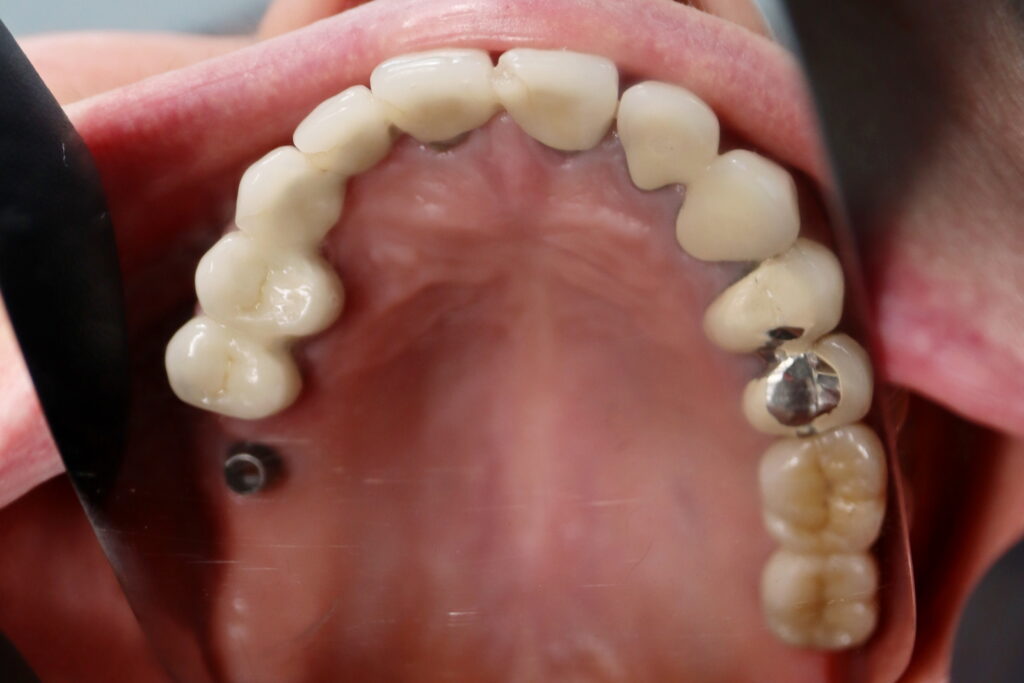

Результаты

результат имплантации